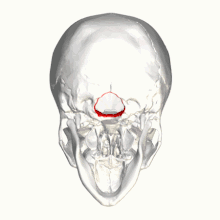

تشوه خياري والذي يعرف أيضا بـ:تشوه آرنولد خياري (بالإنجليزية: Arnold–Chiari malformation) أو (ACM) هو حالة مرضية تحدث عند وجود تشوه خلقي نادر يصيب المخيخ وحجرة المخيخ الخلفية أو إذا كان حجم الجمجمة بالغ الصغر مما يؤدي إلى تغيير في موقع اللوزة المخيخية ودفعها نحو الأسفل من خلال الثقبة العظمى وقد يؤدي أحيانا إلى استسقاء رأس غير متواصل[1] نتيجة لانسداد في جريان السائل الدماغي الشوكي.[2][3]